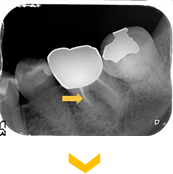

下の奥歯の違和感よ腫脹を主訴に来院。下顎大臼歯の根管内の感染物質を除去した後、徹底的に洗浄消毒を行い、炎症症状の消失となった。

根管治療終了後。炎症症状は無くなり、骨の回復も認められる。

根管治療終了後。炎症症状は無くなり、骨の回復も認められる。